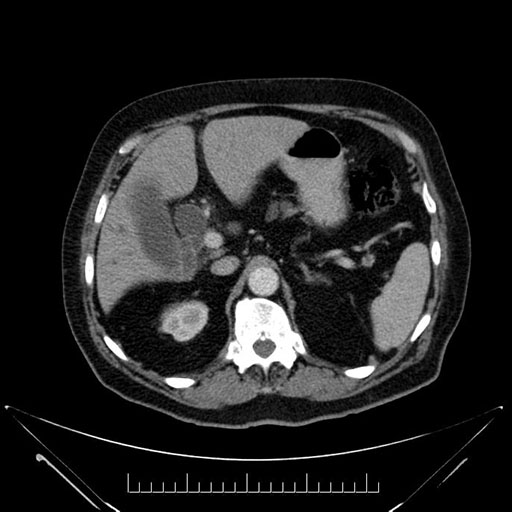

Whipple (pancreaticoduodenectomy) [case 7]

Imaging Analysis

Look through the patient's CT scan to identify any areas of concern for the necessary procedure.

Axial - stented